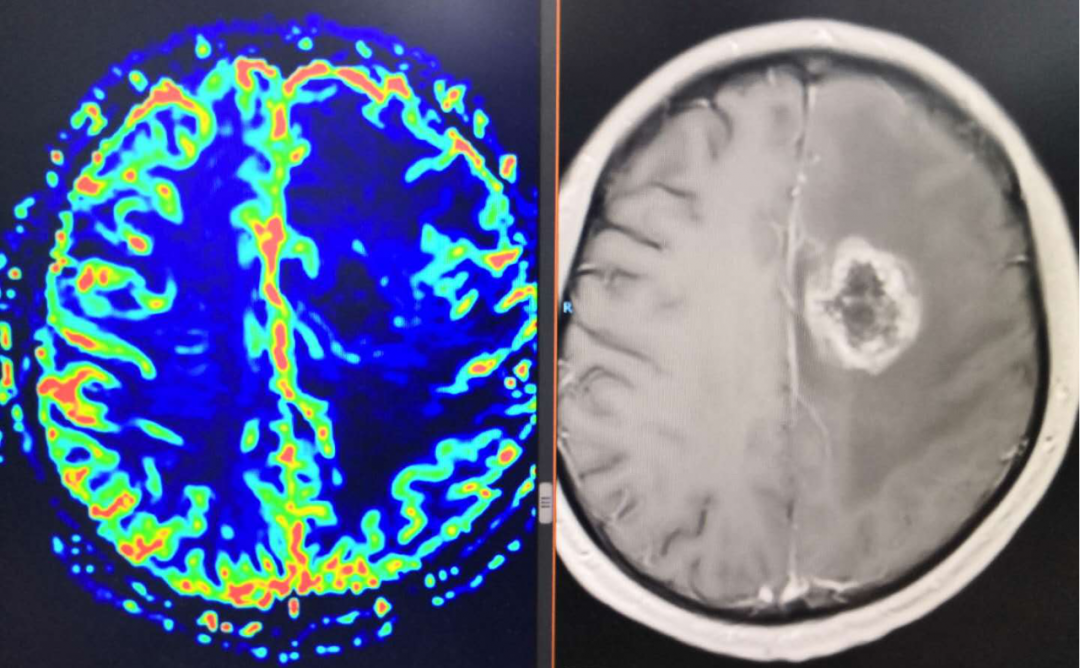

从术前核磁上看左侧额顶叶水肿范围较大,但是从增强上看似乎有强化,内囊前肢前上方有占位, Cho显示是升高的,考虑是肿瘤改变。

复查MRI提示:局部病灶强化,PWI提示局部灌注有缺失,考虑病情进展,同时不除外假性进展,患者脑水肿范围较大。

根据以往经验调整治疗方案:1、根据复发胶质瘤相关指南,首选抗血管生成药治疗;2、MDT讨论:病灶累积胼胝体,再次手术难度大;3、给予“阿帕替尼425mg qd po”。之后显示水肿变小,灌注降低。继续原方案治疗。